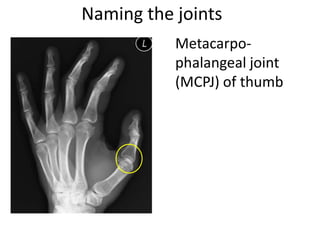

This document provides an overview of hand anatomy including:

- Naming the bones, joints, tendons, nerves and skin landmarks of the hand and wrist.